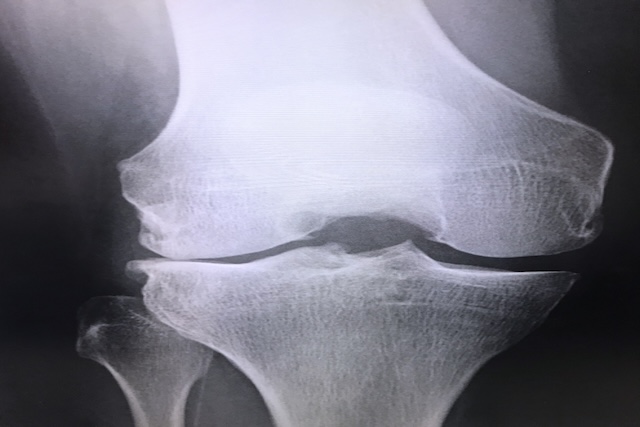

腰の痛みやしびれで医療機関を来院すると、まず行われることが多いのがレントゲン検査です。レントゲンでは骨の状態を明瞭に映し出すことができるため、骨棘の有無や大きさ、形状を確認することができます。

椎体のどの部分に骨棘が形成されているか、椎骨のずれや変形がないかなど、骨の構造的な問題を把握するのに有効な検査といえるでしょう。ただしレントゲンでは神経や椎間板といった軟部組織は映らないため、骨の状態しかわからないという限界もあります。